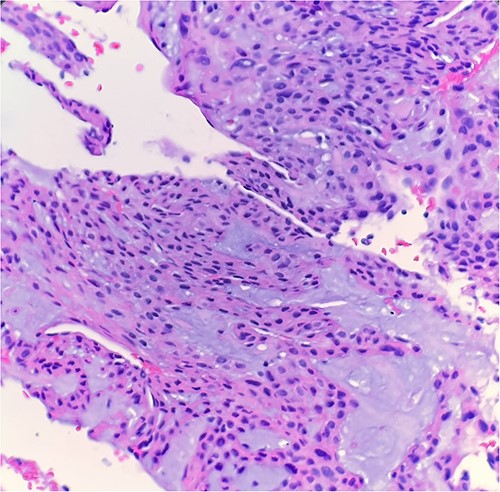

The excised mass was a fragment of tan red soft tissue measuring 0.7 × 0.4 × 0.4 cm. Microscopic examination reveals that tumor is composed of epithelioid bland cells forming gland-like architecture with scant mucinous material (Fig. 1). Without immunohistochemical stain, the morphological features are diagnostic for adenocarcinoma. However, in order to rule out other diagnostic possibility, we performed smooth muscle actin (SMA) immunohistochemical stain. The tumor cells turn out to be positive for SMA (Fig. 2). Combined with this immunoprofile, the final diagnosis of glomus tumor was rendered. The diagnosis of glomus tumor was confirmed with second opinion at world renowned institute.

Immunohistochemical stain reveals that tumor cells are positive for SMA. IHC ×20.

Careful evaluation of the pathological findings is essential to distinguish between glomus tumors and adenocarcinoma. SMA is a specific marker with 99% specificity for the diagnosis of glomus tumor [2]. SMA is commonly used to identify myoepithelial cells, smooth muscle cells and myofibroblasts in normal, reactive or neoplastic tissue, which should not be seen in adenocarcinoma [9]. In our report, the initial evaluation on morphology suggested adenocarcinoma because of glandular like structures. Because of the positive of SMA, the final diagnosis of glomus tumor was made. Further studies including immunohistochemical stain are necessary to fully understand the histological similarities and dissimilarities between the two types of tumors, in order to differentiate the benign lesions from malignant neoplasms.